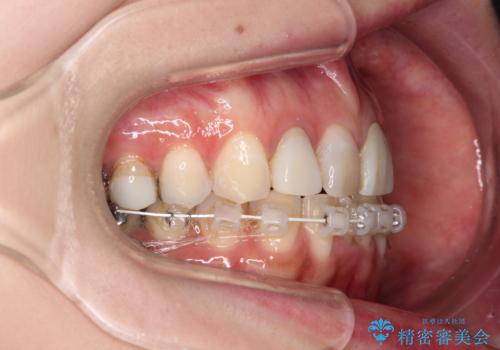

インプラント部は治癒待ちの期間が長くなるため、その期間を利用して下顎の叢生を解消し、より理想的な咬み合わせで補綴治療を行うこととしました。

途中通院されなかった時期が何度かあったため、初診から4年以上の年月がかかりましたが、比較的スムーズに治療を進めることができました。

下顎前歯の歯列を整えたことで、上顎前歯の咬み合わせが安定し、自然な口元に仕上げることができました。